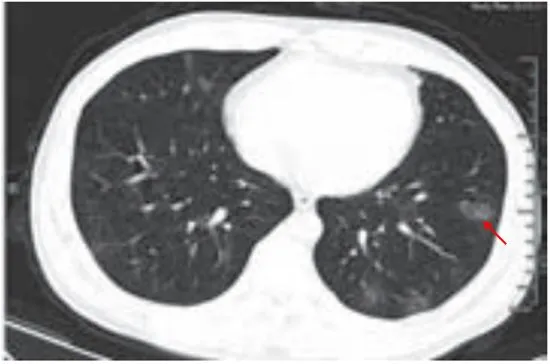

(一)病灶分布

病灶以肺外围背侧为主,以两肺下叶为著,与胸膜常紧贴,提示新冠肺炎病变多首先侵犯皮层肺组织的细支气管及肺泡上皮,病灶分布逐步从外周向中央扩展(图 2-1)

图2-1 早期病灶多数分布贴近胸膜(共4张)